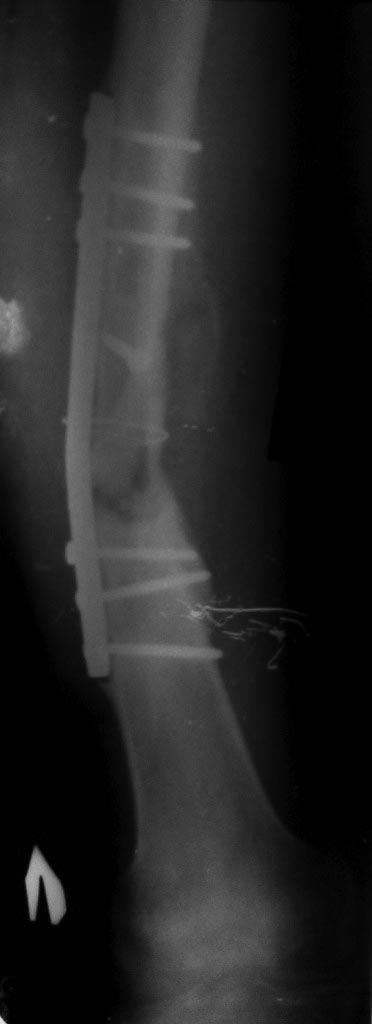

Уважаемые коллеги! Помогите определиться с тактикой лечения у молодого

пациента.

Молодой парень, 25лет. Травму получил в ноябре 2012 года, ДТП.Оперирован

в сельской больнице, остеосинтез перелома бедренной кости пластиной и

АВФ на голень с этой стороны, наложена гипсовая повязка коксит на 3

месяца. В момент госпитализации разгибательная контрактура коленного

сустава (движения в коленном суставе сгибание 10 градусов) 02.07.2013

произведена операция - удаление металоконструкции с бедренной кости,

костная аутопластика( из подвздошной кости) и БИОС бедренной кости

универсальным гвоздем ChM. ЭОПа у нас нет, пользуемся переносным

рентгенапаратом. Как быть с ложным суставом голени?